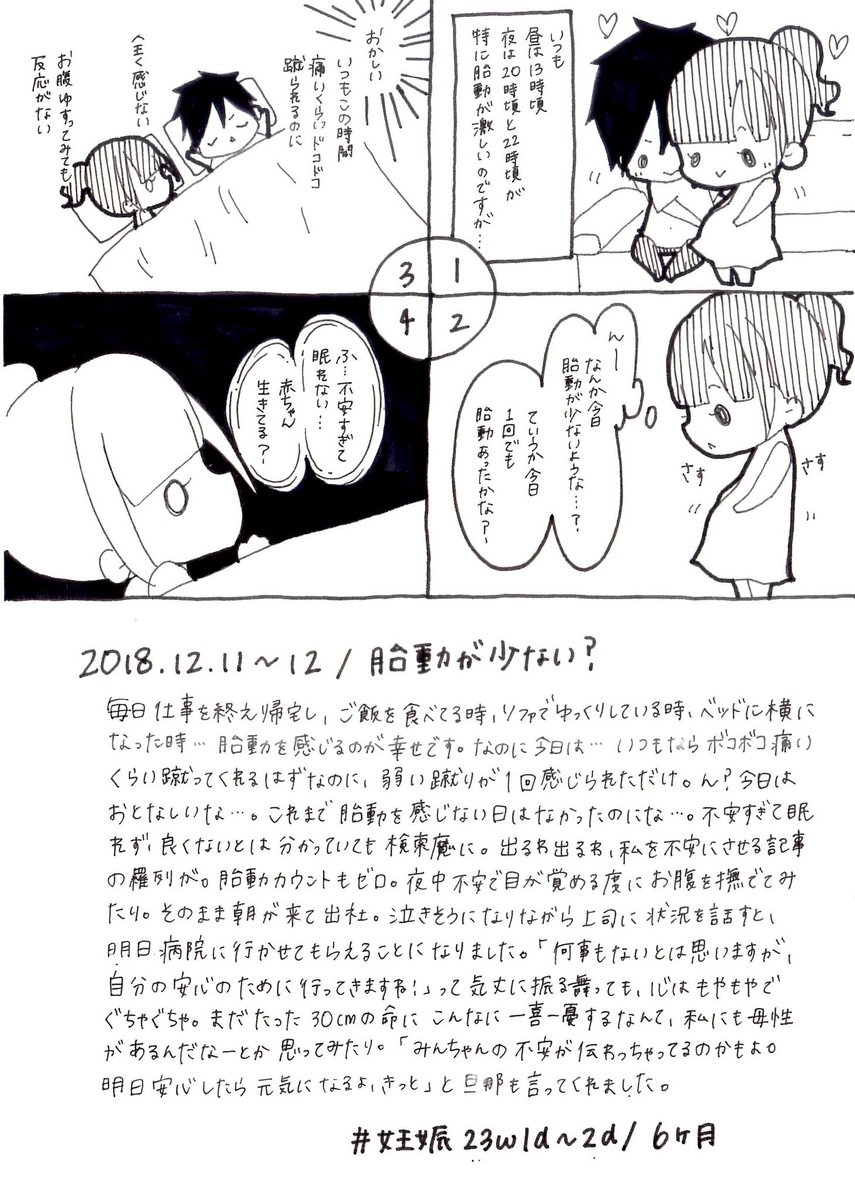

2018.12.11 いつも痛いくらいの胎動、丸1日感じなかった日がありました。 見逃しただけ?いや、やっぱり何かおかしい…ということで、病院へ行くことに。 赤ちゃん、どうか無事でいて! #育児漫画 #育児日記 #妊娠 #妊娠中期 #胎動 #妊娠6ヶ月 #イラスト好きさんと繋がりたい #ママ垢さんと繋がりたい pic.twitter.com/zO0oJrfS9b

拡大

2018.12.12 丸1日以上経っても胎動が感じられないように思い、不安でいてもたってもいられず意を決して病院へ。 ママと赤ちゃんは文字通り一心同体だからね。不安が赤ちゃんにも伝わっちゃってたのかも。 #育児漫画 #育児日記 #妊娠 #妊娠中期 #胎動 #エコー #妊娠6ヶ月 #ママ垢さんと繋がりたい pic.twitter.com/uvQfJcuudI

拡大